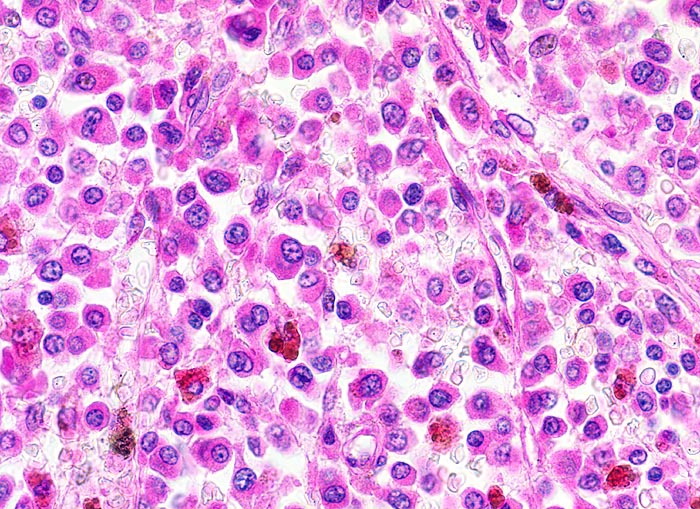

Knochenmarkstanze mit nodulärer Hyperzellularität des blutbildenden Marks.

Keine wesentliche Osteopenie.

In den hyperzellulären Arealen dichte Rasen neoplastischer atypischer Plasmazellen.

In dieser Giemsa-Färbung sind die Plasmazellen gut erkennbar. Die Plasmazellen sind polymorph, vereinzelt mehrkernig. Exzentrisch im Zytoplasma lokalisierte vergrösserte Radspeichenkerne . Reichlich violettes Zytoplasma mit paranukleärer Aufhellung. Zellkerne teils mit vergrössertem Nukleolus.

Ausserhalb der Plasmazellrasen findet sich spärlich residuelles blutbildendes Knochenmark.